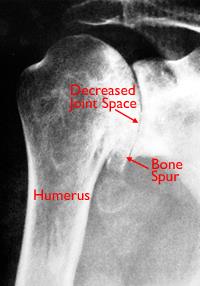

The successful diagnosis and treatment of glenohumeral arthrosis in the young and active patient can be challenging to even the most experienced of clinicians. As the smooth cushion between the humeral head and glenoid erodes the bones begin to grind against one another. Typical of arthritis glenohumeral osteoarthritis causes symptoms such as pain stiffness limited joint function and range of motion in the shoulder.

The glenohumeral joint is the third-most common large joint affected by degenerative joint disease. Glenohumeral arthritis is degenerative joint disease of the shoulder characterized by damage to the articular surfaces of the humeral head andor glenoid.

In degenerative joint disease DJD the glenoid cartilage and subchondral bone are typically worn posteriorly often leaving intact articular cartilage anteriorly see figure 4. 1Department of Orthopaedics University of Washington Medical Center Seattle 98195 USA. Findings of a hill-sachs deformity.

Primary glenohumeral degenerative joint disease. Most people above 60 years have some degree of OA which is a top cause of disability in older people. Degenerative joint disease also known as osteoarthritis or osteoarthrosis is a common type of glenohumeral arthritis in which the articular cartilage fails from heavy use cumulative minor traumatic episodes underlying structural defects in the joint anomalies in cartilage composition or a combination of these factors.